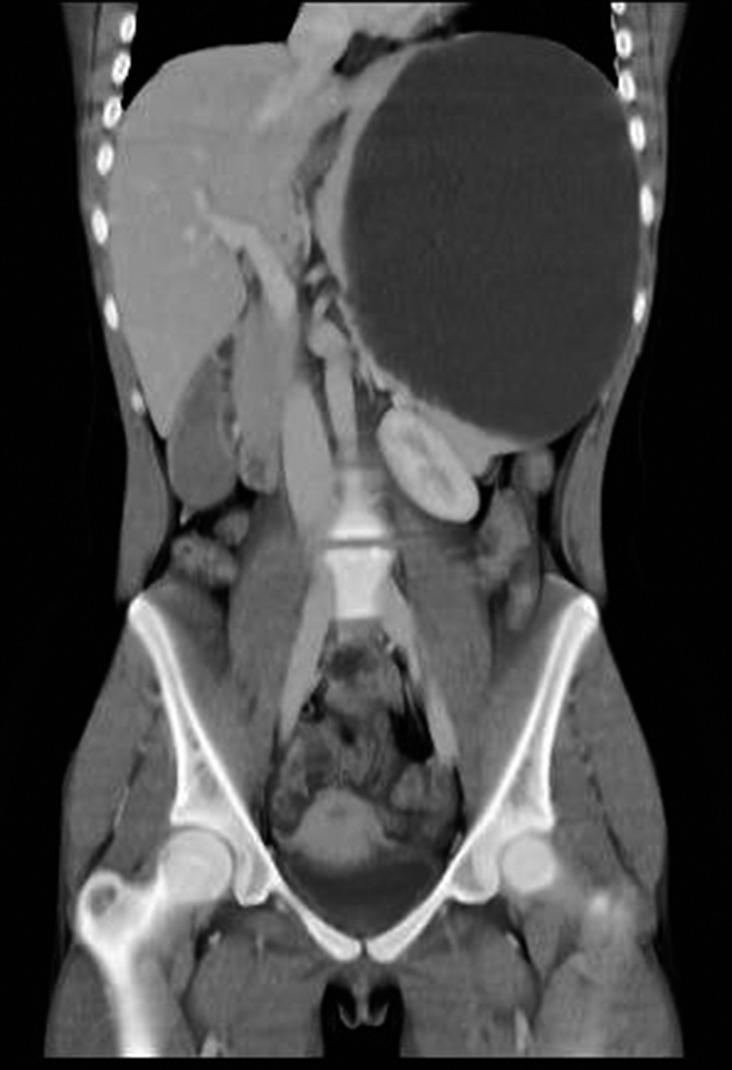

Partial splenectomy for a giant epidermoid cyst of the spleen.

The splenic epidermoid cysts are rare benign tumors, and a definitive treatment remains unclear. Although some spleen-preserving approaches have been reportedly used, splenic cyst recurrence usually occurs in true cyst cases, wherein the cyst is incompletely removed. In our case, partial splenectomy was performed and the giant cyst was completely removed.